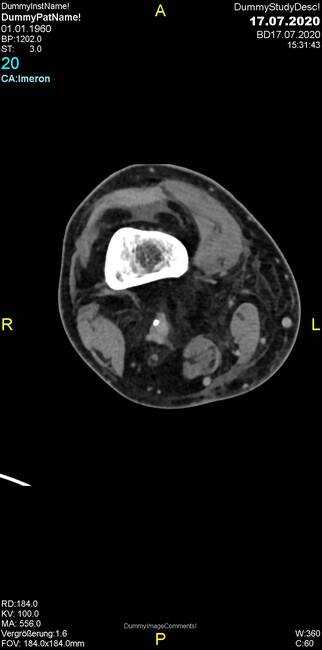

Um welche Modalitäten handelt es sich?

- Röntgen p.a. und lateral, CT coronar Knochenfenster, CT axial Weichgewebsfenster

- Röntgen p.a. und lateral, CT coronar Weichgewebsfenster, MR axial

Was fällt in der Projektionsradiographie auf?

- Verdichtung im Recessus suprapatellaris

- Aufhellungslinie in Projektion auf die Femurkondylen

- Erhöhter tibialer Slope

- Hypertransparenz tibial

- Subluxationsstellung im Kniegelenk

Was trifft auf den Befund zu?

- Der Befund beschränkt sich auf den Knochen.

- Es besteht hochakuter Handlungsbedarf.

- Der Befund ist tendenziell benigne.

- Der Befund ist tendenziell maligne.

- Der Befund weist einen Zusammenhang zum Patientenalter auf.

Was fällt in der CT im Knochenfenster auf?

- Mediale Gelenkspaltverschmälerung

- Dezente Erosion der fibulären Kortikalis

- Frakturspalt der lateralen Tibiametaphyse

- Weichgewebskalzifikationen lateral angrenzend an den Gelenkspalt

- Osteolyse der Tibiametaphyse unter Beteiligung der Kortikalis

Was kommt differentialdiagnostisch in Frage?

- Kompartmentsyndrom

- Osteomyelitis mit Weichgewebsanteil

- Metastase mit pathologischer Fraktur

- Rheumatoide Athritis

- Posttraumatische Verletzung